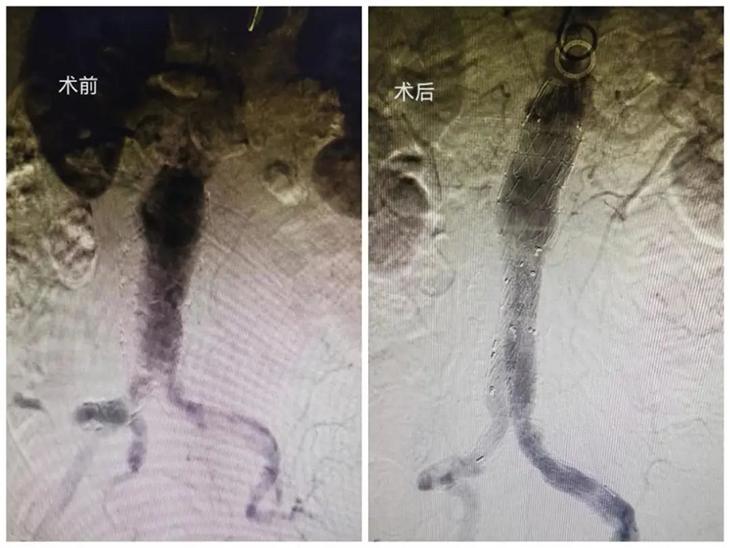

当日下午,经过短暂休整,手术团队再接再厉,又接连进行了两例腹主动脉瘤腔内隔绝手术。由于其中一位患者血管迂曲严重,瘤体大,手术操作难度大大增加。但凭借丰富的手术经验和娴熟的技术手法,手术成功完成,支架形态良好,血流通畅。

腹主动脉瘤支架腔内隔绝术

腹主动脉瘤是一种高致命的危险疾病,随时都有破裂大出血的危险,一旦破裂出血可危及生命,又被称作“人体内定时炸弹”。腹主动脉瘤支架腔内隔绝术是将覆膜支架导入腹主动脉,将腹主动脉瘤与血管腔隔绝,促使其逐渐机化、缩小,从而消除瘤体破裂、出血的隐患,达到治愈的目的。因其治疗创伤小、恢复快,是近年发展起来的治疗腹主动脉瘤的一种新方法。